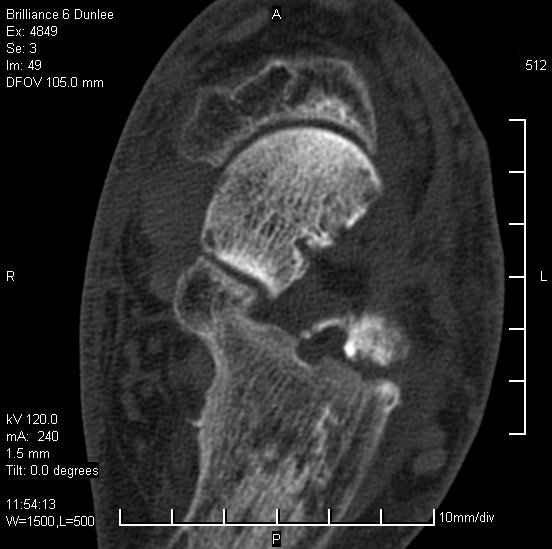

Асептический некроз таранной кости.

На лечении находится пациент 35 лет. Травма в сентябре 2008 г.- открытый вывих таранной кости

В день травмы ПХО, вправление вывиха, трансартикулярная фиксация. Рана зажила первично. С января нагрузка на конечность. С конца апреля- болевой синдром. На рентгенограммах и КТ признаки ас. некроза таранной кости, артроз подтаранного и голеностопного суставов.